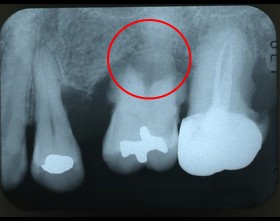

根尖病変(根の先の病気)

口腔内写真とデジタルXray写真(2次元)

CT 3D画像

3枚の写真赤丸部分が根尖病変(根の先の病気)です。

根の先に膿がたまっています。

デンタルXray写真(2次元画像)では理解しづらい根の先の骨吸収がCT画像(3次元画像)により明瞭に認められ確実な診査・診断が出来、患者さんの理解も容易になり1つの目標に向かって歯科医と患者が一体となりスムーズに治療を進めることが出来ます。